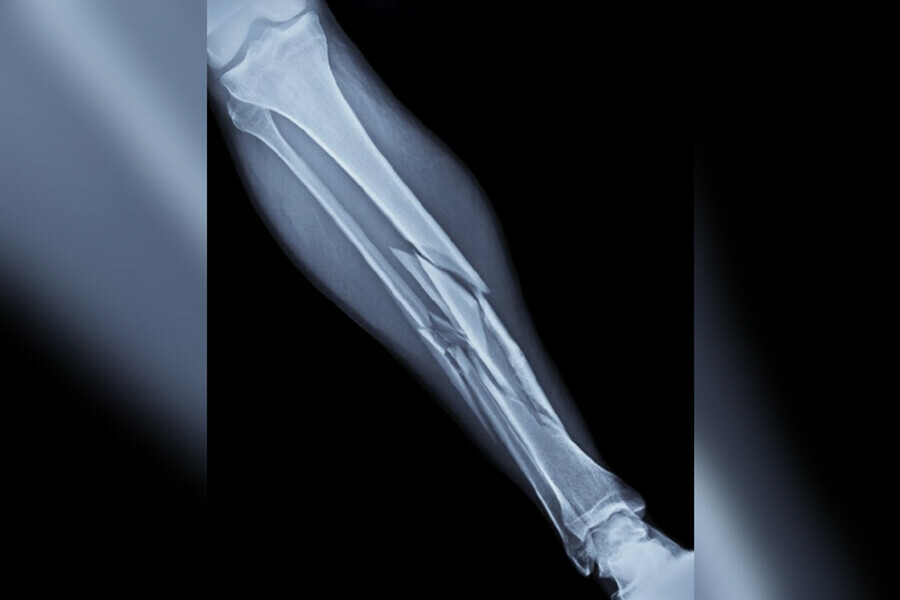

12 марта в инспекцию труда в Амурской области поступило извещение о произошедшем тяжелом несчастном случае с работником ООО «Сварочно-монтажная компания». Он получил тяжелую травму ноги.

Работодатель сообщил, что ночью 12 марта монтажник технологических трубопроводов в составе бригады работал на строительной площадке ООО «Амурский ГХК». При перемещении двух металлоконструкций он был рядом, и одна из них опрокинулась и упала на его левую ногу. Работника отправили в медицинское учреждение – согласно заключению врачей пострадавший получил тяжелую травму.